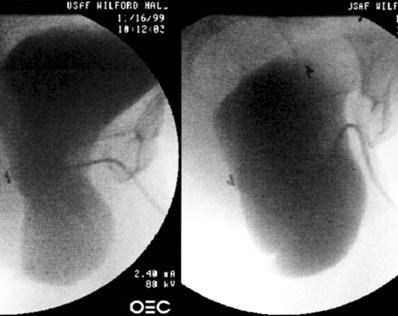

Figure 75–2 In this lateral fluoroscopic view, taken during urodynamics, the bladder is seen to prolapse significantly with Valsalva maneuver, with severe kinking of the urethra causing obstruction. When this prolapse is reduced during examination, the urethra is straightened, and occult incontinence may be elicited.